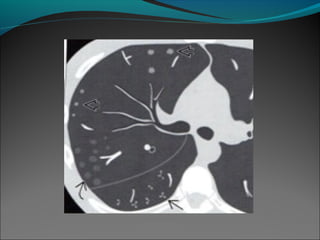

Enfermedad de las vías aéreas grandes (dilatación crónica

e irreversible del bronquio).

El signo principal es la dilatación bronquial que no

disminuye su calibre a medida que se dirigen hacia la

periferia; con o sin engrosamiento de la pared bronquial.

Se sugiere para la correcta evaluación utilizar secciones de

1.5 mm a intervalos de 10 mm con un algoritmo de

reconstrucción espacial de alta resolución. Con un tiempo

de adquisición rápido (para reducir los artefactos causados

por el movimiento involuntario del paciente).

Las vías aéreas identificadas antes de 1 cm de la pleura

costal o de la pleura paravertebral deben verse como

bronquiectásicas.

Pueden ser cilíndricas, saculares y/o varicosas.